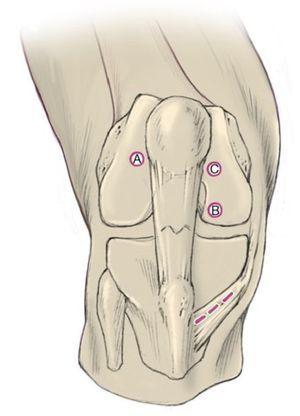

Fig. 3 El portal de perforación medial se encuentra justo por encima del cuerno anterior del menisco interno. Se perfora siempre con la técnica de aguja hipodérmica. Conviene que el abordaje no se encuentre demasiado hacia medial para que la broca no lesione el cartílago del cóndilo femoral medial. Si, por el contrario, el túnel se encuentra demasiado lateral, la broca puede salir del túnel por la parte posterior.